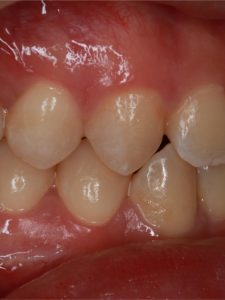

Jaw Repositioning (Orthognathic) Surgery

Before and After Images